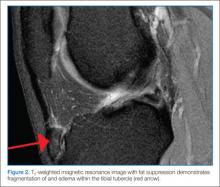

Evaluation of suspected osteomyelitis begins with plain radiographs, CBC, ESR, and CRP. Elevated inflammatory markers are sensitive but not specific for osteomyelitis and may be followed serially to determine response to treatment. Blood cultures should also be obtained and are positive in up to 50% of cases of acute osteomyelitis. Plain radiographs are frequently nondiagnostic early in the course of disease and should primarily be used to evaluate for other causes of joint pain such as fracture or malignancy. The imaging modality of choice is MRI as it is capable of detecting early inflammatory changes in the bone; fast sequence MRIs are now used to screen for osteomyelitis in an attempt to reduce the need for sedation in young children (Figure 2).11Ideally, antibiotic therapy should be deferred until cultures from the site of infection are obtained operatively or via aspiration. The local staphylococcus aureus resistance pattern should guide empiric antibiotic therapy. With the rise of MRSA, clindamycin has become first-line therapy with vancomycin as an alternative for severely-ill or clindamycin-allergic patients. For children younger than 3 years of age with a more subacute presentation, the possibility of Kingella infection should be considered and treated with a cephalosporin. Some children with osteomyelitis will require operative debridement, though